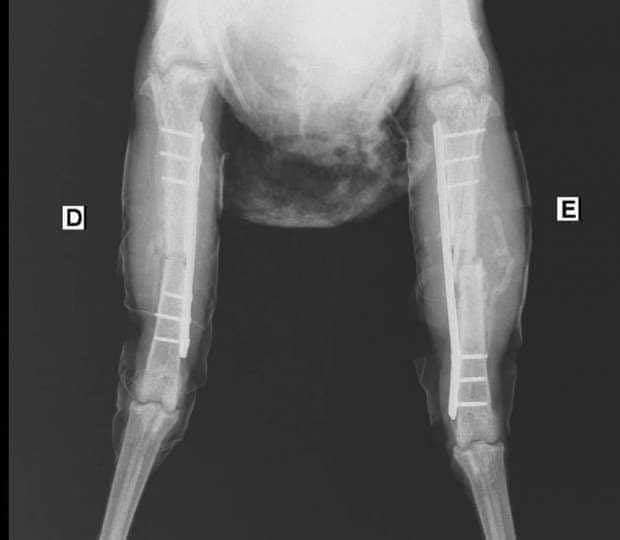

وكان طبيبان بيطريان قد أجريا عملية جراحية لـ"فرخة" بها كسر وتم تركيب شرائح ومسامير طبية لها ويطلق عليها اسم "ليكسي" ووضعت تحت الملاحظة، وتم وضعها على أجهزة وتركيب محاليل لها كبديل عن الطعام. (سبوتنيك)